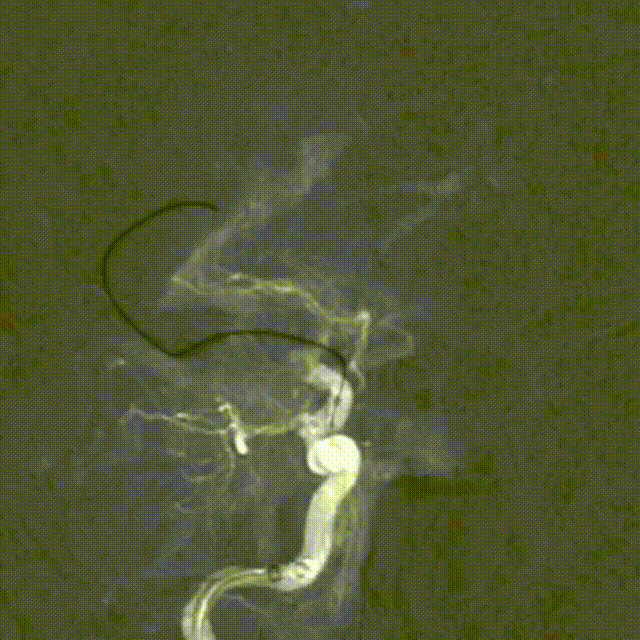

再次释放Syphonet®取栓支架 5*35mm,造影显示:支架释放效应阳性。

M1局部重度狭窄。

SacSpeed®球囊扩张导管 2.0*9mm球囊到位过程。